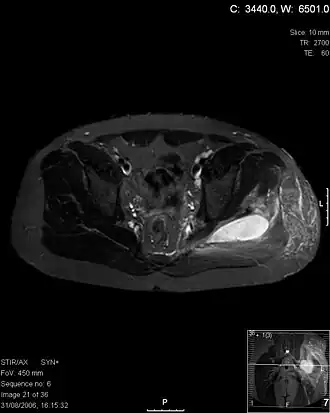

![]() Imagen por resonancia magnética (corte transversal en T2 a nivel de la pelvis) de piomiositis de los músculos glúteo mayor y medio. | ||